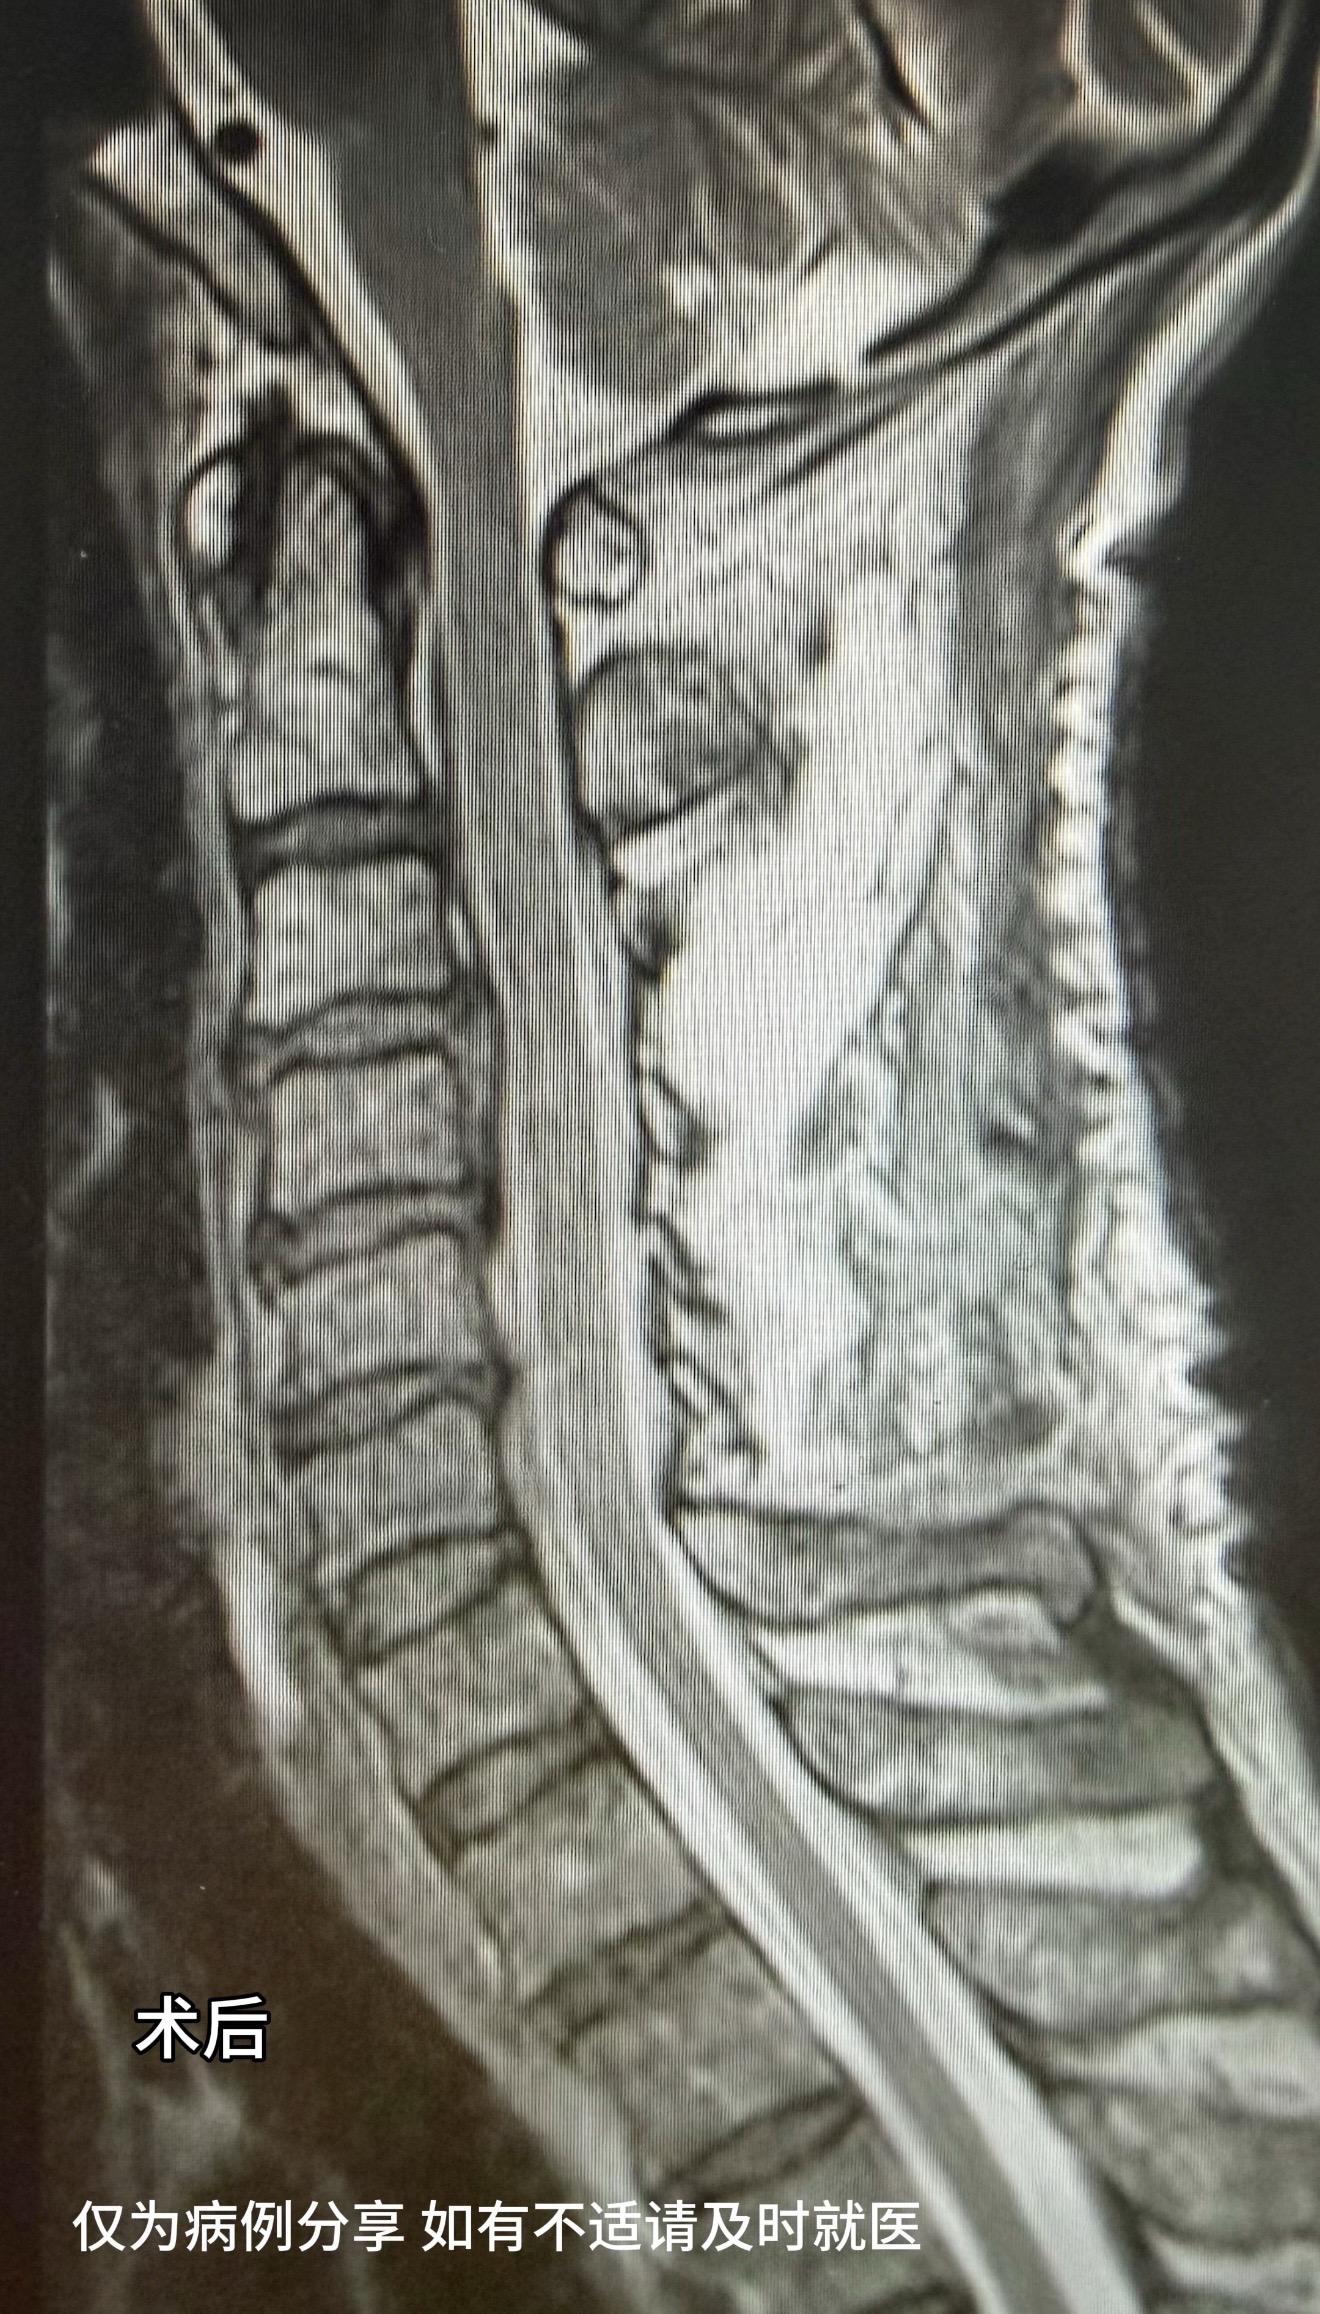

60多岁男性,工地颈椎外伤,伤后双手握力下降,右手握力2级,持碗筷不能,生活受限明显。术后6天,右手握力恢复至4级弱,能持碗筷,患者及家属非常满意。